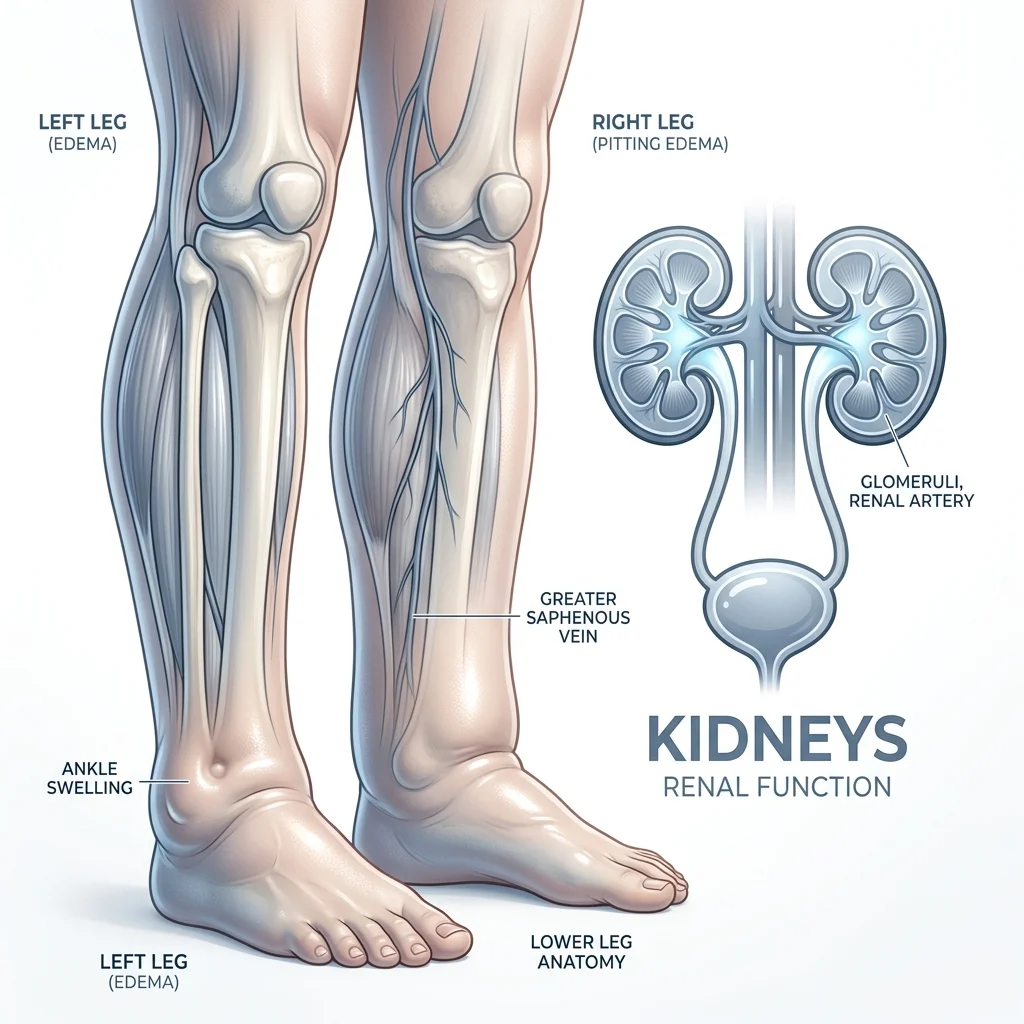

Inchaço, fadiga e alterações na urina: aprenda a identificar os alertas silenciosos e proteja sua saúde renal.

O inchaço persistente pode ser um alerta precoce de falha renal. Saiba como identificar o edema renal.